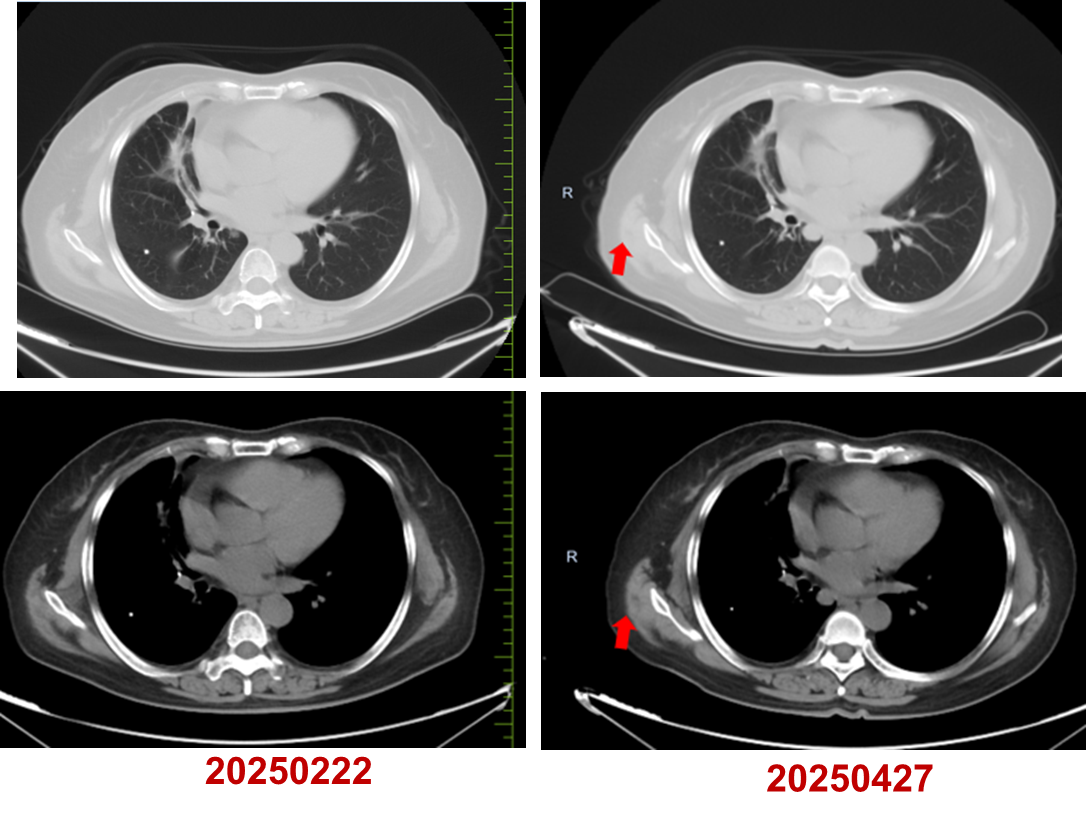

2024年7月至2025年4月,行长春瑞滨软胶囊(40mg,每周一、三、五)口服治疗。

疗效评估:PR。

基于上述证据并尊重患者意愿,本例患者三线采用口服长春瑞滨节拍化疗,疗效评估达到PR。截至末次随访时间(2025年4月),患者连续用药9个月余,无明显不良反应,疾病控制稳定,初步实现晚期肺癌的长期慢病化管理。